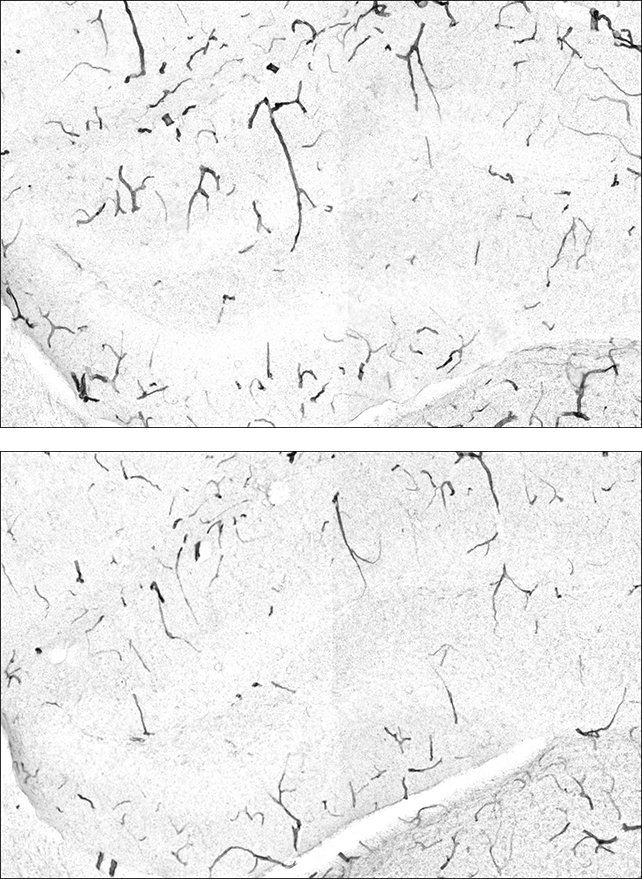

دراسة حديثة قادتها جامعة كاليفورنيا في سان فرانسيسكو (UCSF) ربطت بين GPLD1 وإنزيم TNAP. هذا الإنزيم عادةً يجعل حاجز الدماغ الواقي «نفاذاً» عندما تتعرض الظروف للضغط. ضغط الحياة اليومي في بلداننا العربية يجعل هذا الأمر أكثر أهمية.

يتراكم TNAP مع الوقت داخل خلايا حاجز الدماغ، يعطل وظيفتها. الدراسة وجدت أن GPLD1 «يزيل» TNAP من الأنسجة. يعزز حماية الدماغ من الالتهاب. معركة داخلية صامتة يحسمها الجسم.

فئران مسنة عُدلت وراثياً لخفض TNAP. تراجعت تسربات حاجز الدماغ، وقلت الالتهابات، وتحسنت قدراتها العقلية بشكل ملحوظ.

في فئران مصابة بالزهايمر، زيادة مستويات GPLD1 أو خفض مستويات TNAP ارتبط بوجود تكتلات أقل من بروتين «أميلويد بيتا» الضار، وهي علامة مميزة لمرض الزهايمر. هذا مؤشر إيجابي آخر.

يعرف جيداً أن الالتهاب أو إجهاد الخلايا العصبية يلعب دوراً رئيسياً في الزهايمر وجوانب أخرى من شيخوخة الدماغ وتدهور القدرات العقلية. حاجز الدماغ يحمي من المواد الكيميائية التي قد تثير ذلك الالتهاب.